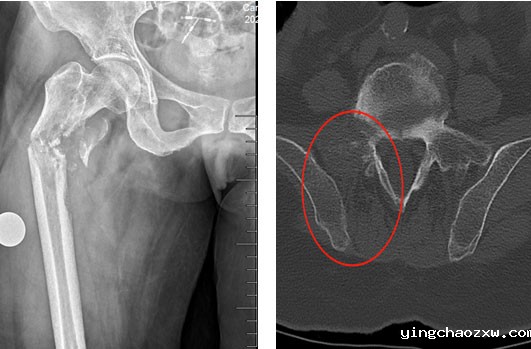

近日,新利官网登录西院区骨伤科收治了一名特殊53岁女性肺部恶性肿瘤患者,本次入院因扭伤致右侧大腿肿痛、畸形、活动障碍入院。入院检查后明确患者为右侧股骨上段骨折,骨折端周围有骨质破坏伴全身多处骨转移征象。考虑患者右侧股骨上段骨折为肺肿瘤骨转移导致右侧股骨骨质破坏,骨质强度降低,轻微外力后导致右股骨病理性骨折。

县总医院骨科团队综合研判患者病情,及时制定合理、安全、有效的治疗方案,决定为患者行右侧股骨骨肿瘤切除,肿瘤型人工髋关节置换术。因患者右股骨髓腔细小,常规人工髋关节体假体无法使用,需使用特殊假体,根据患者DR、CT,向生产厂家为患者量身定做了个性化定制型人工肿瘤髋关节假体,征对患者髓腔细,假体特别设计了个性化结合部加强套筒,确保假体强度及使用安全,术前行右下肢动脉CTA,严格评估右股骨肿瘤营养动脉血供情况,避免术中出现难以控制出血,经精心准备,在主任医师陈志强院长带领下,总医院骨科近日成功为患者实施了右侧股骨近端恶性肿瘤骨转移切除、定制肿瘤型人工髋关节置换术。手术历时2小时完成,术中患者病情平稳,术后患者疼痛疼痛消除,右下肢活动明显改善,患者的生活质量得到了极大提高,家属也十分满意。